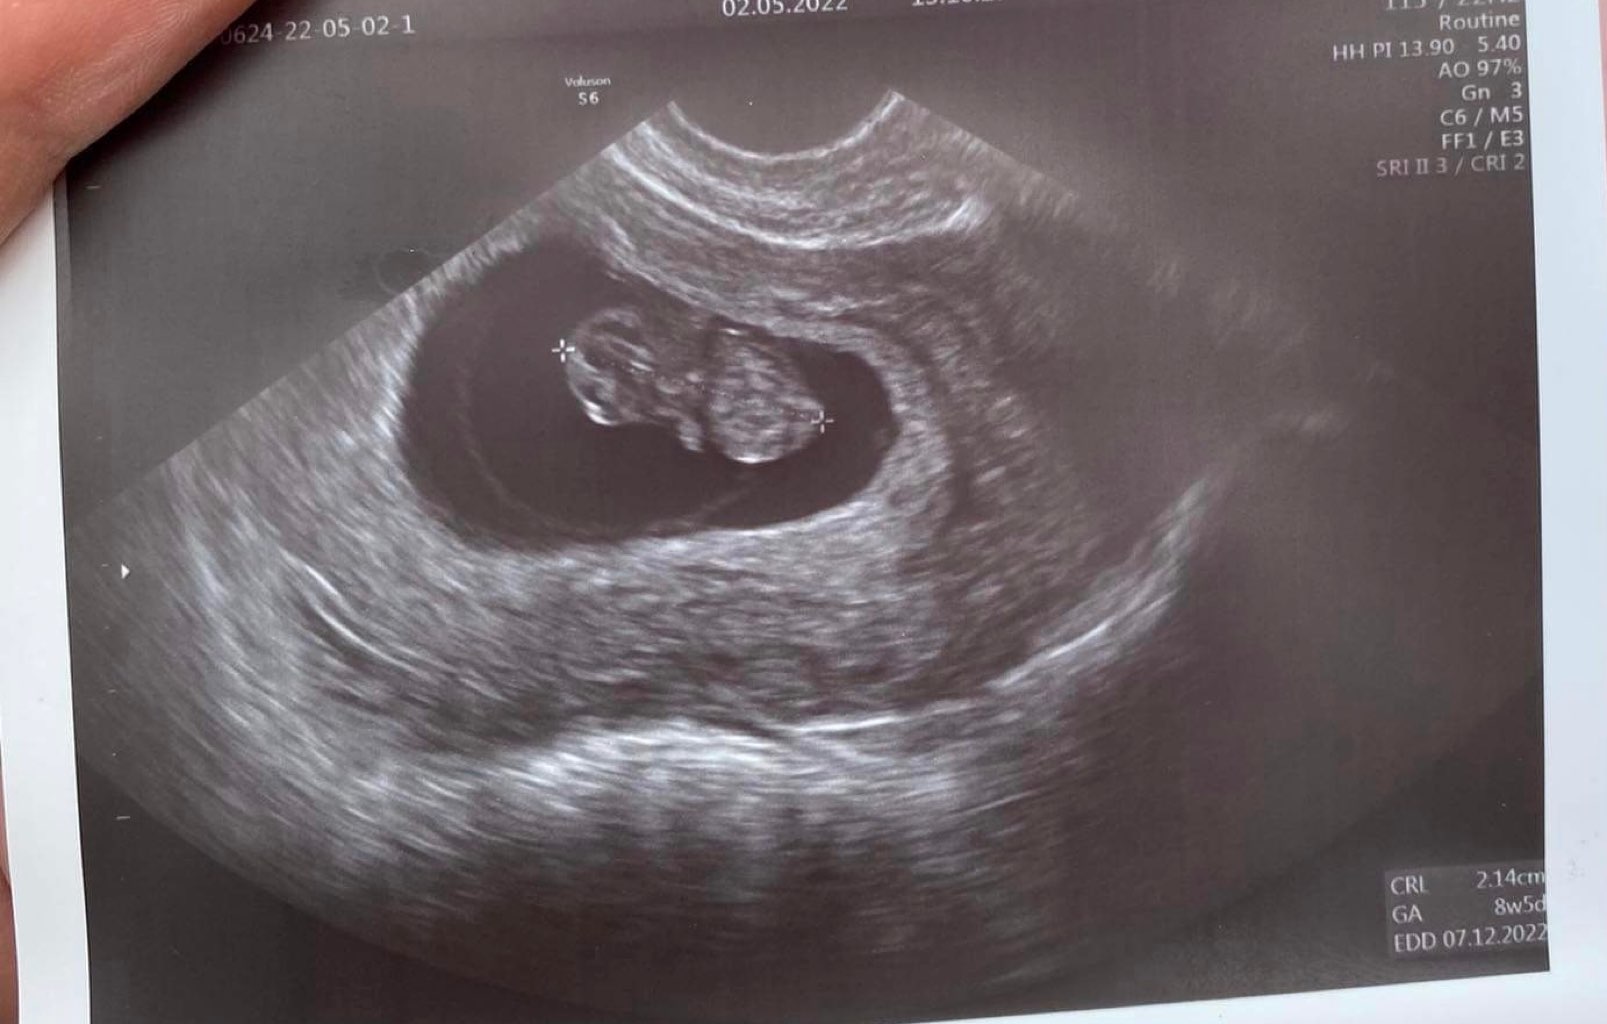

Zgłaszamy się po wizycie razem z fasolą!

Wszystko pięknie, ciąża o 2 dni młodsza niż z OM.

Teraz czekam na prenatalne 24.05 🤞🏻❤️

Załączniki

• IMG_9266.jpg

IMG_9266.jpg

147,7 KB · Wyświetleń: 106